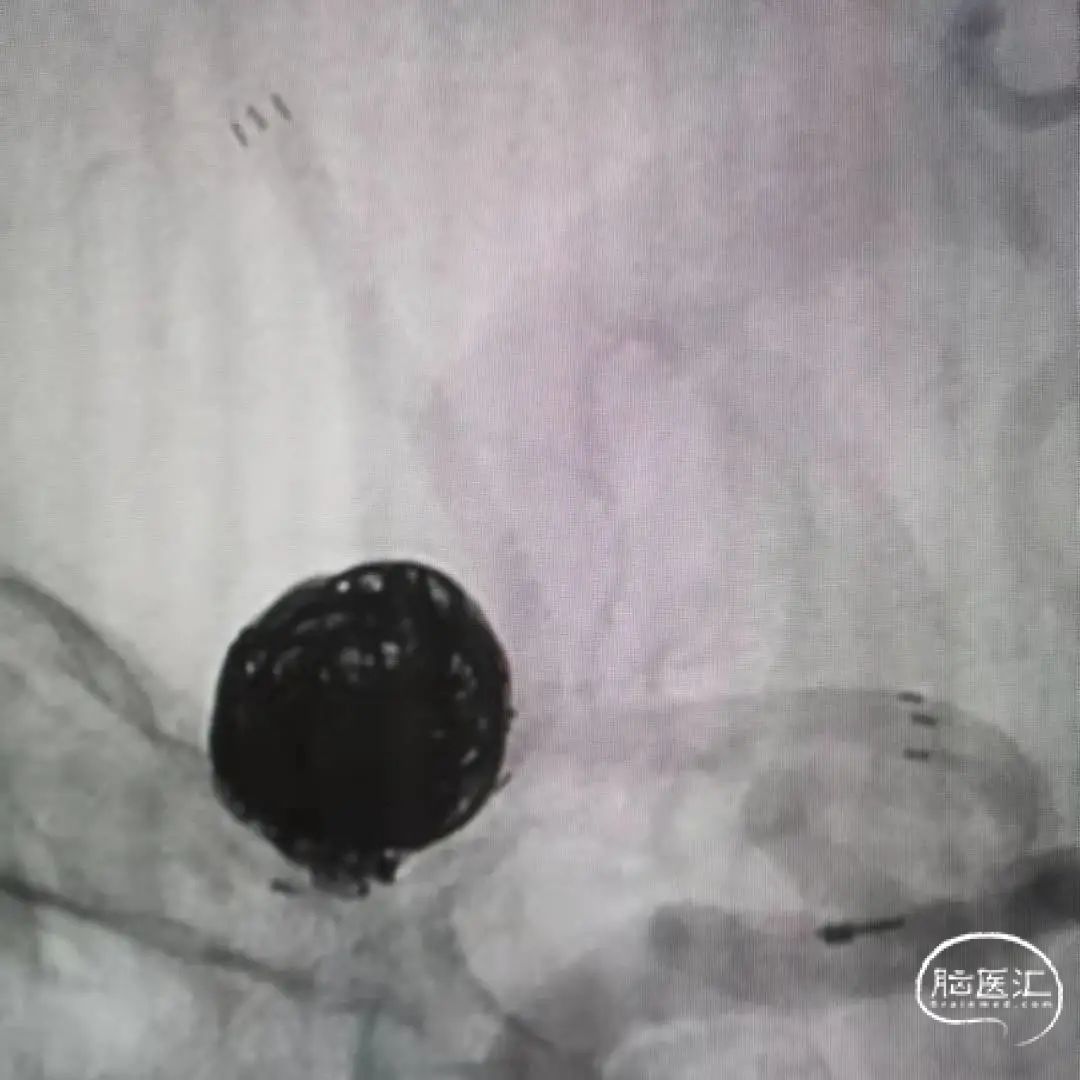

术前3D-DSA造影:测量动脉瘤直径在12mm,载瘤动脉直径1.85mm。

首先选取200cm Synchro 2微导丝将直头微导管,预置在同侧大脑前动脉。由于对侧A1段过细且迂曲,因此放弃前交通横行支架方案,采取T型支架方案。Atlas支架精准的定位释放,才是T型支架成功的关键。

支架释放过程:固定支架推送导丝,回撤45°微导管,最终完成3.0mm*24mm Atlas支架的释放。

将3.0mm*21mm Atlas支架释放到同侧大脑前动脉A2段,近端衔接在第一个支架的体部,使两个支架形成T型结构,然后将弹簧圈解脱。

术后即刻正侧位造影显示:小阜及瘤体致密栓塞,支架贴壁和导流良好。